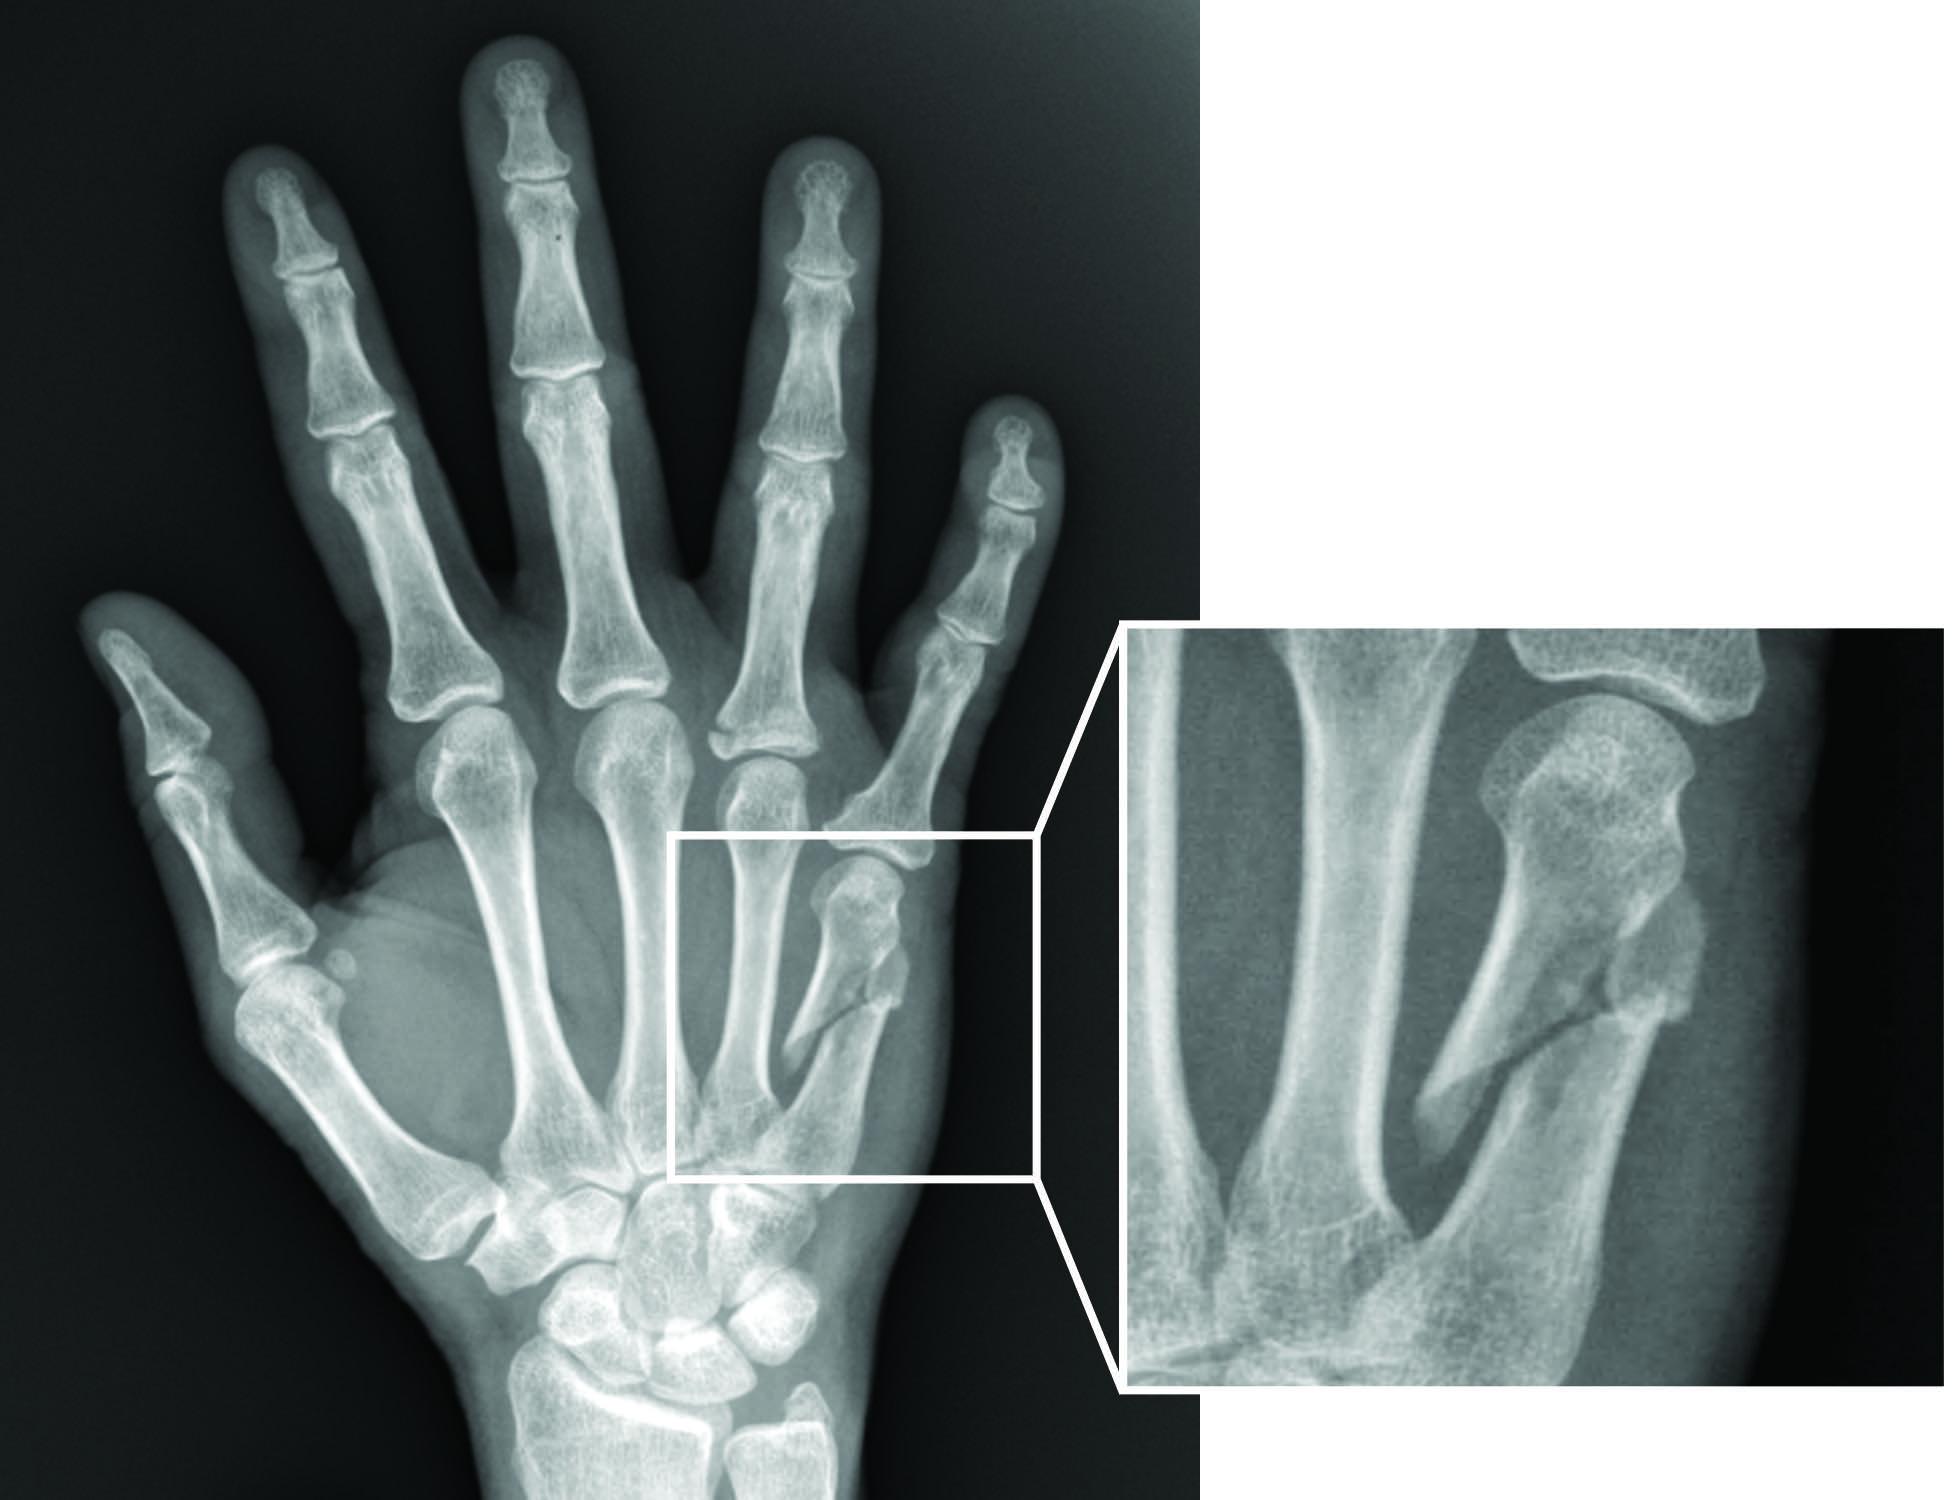

25歲黃先生,因跌倒造成右手中指腫痛,導致工作及生活都受到很大的影響,就醫後以X光仔細定位病灶處,依手指正面及側面的影像,診斷為右手中指中段指骨基底骨折,並採用新設計的「微型互鎖式骨板」加上手部復健,兩周後黃先生已可活動,六周恢復正常工作。

目前最新的「微型互鎖式骨板」治療,是將骨釘與骨板互鎖,先以拉力及加壓骨釘引導骨頭準確後復位,再以互鎖式骨釘骨板穩固固定。針對手指各部位骨折、複雜性骨折及骨質疏鬆的病人,可使關節活動度不受影響及穩固復位,傷口復原後也不易感染,且愈合時間短,盡速恢復手部活動。復健部職業治療復健團隊並針對每位病人訂定復健計劃及治療,讓病人可以早日恢復功能。